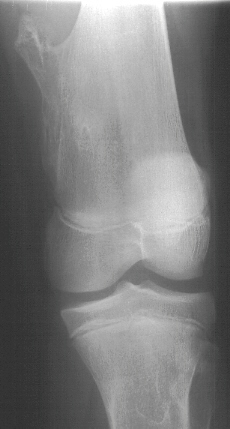

at the medial proximal tibia. X-rays of her left knee in the AP/lat/oblique

views revealed multiple exostoses of the distal femur and proximal tibia.